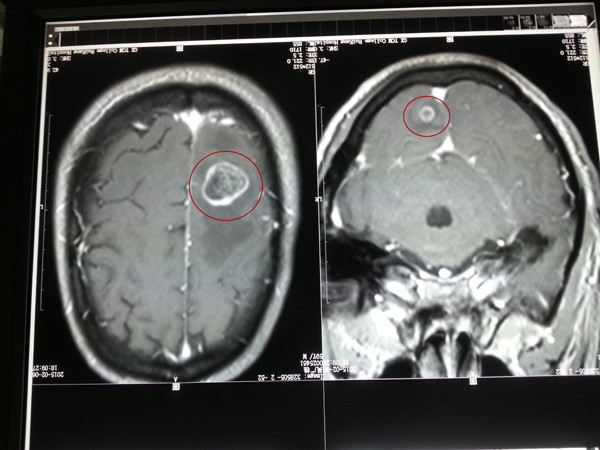

• 肠癌患者术后脑转移致偏瘫射波刀治疗3次肢体功能恢复

肠癌患者术后脑转移致偏瘫射波刀治疗3次肢体功能恢...

近期,广西中医药大学附属瑞康医院放疗科利用射波刀治疗一位肠癌术后脑转移导致偏瘫的患者,经治疗半个月后肢体功能恢复。 家住南宁市的...